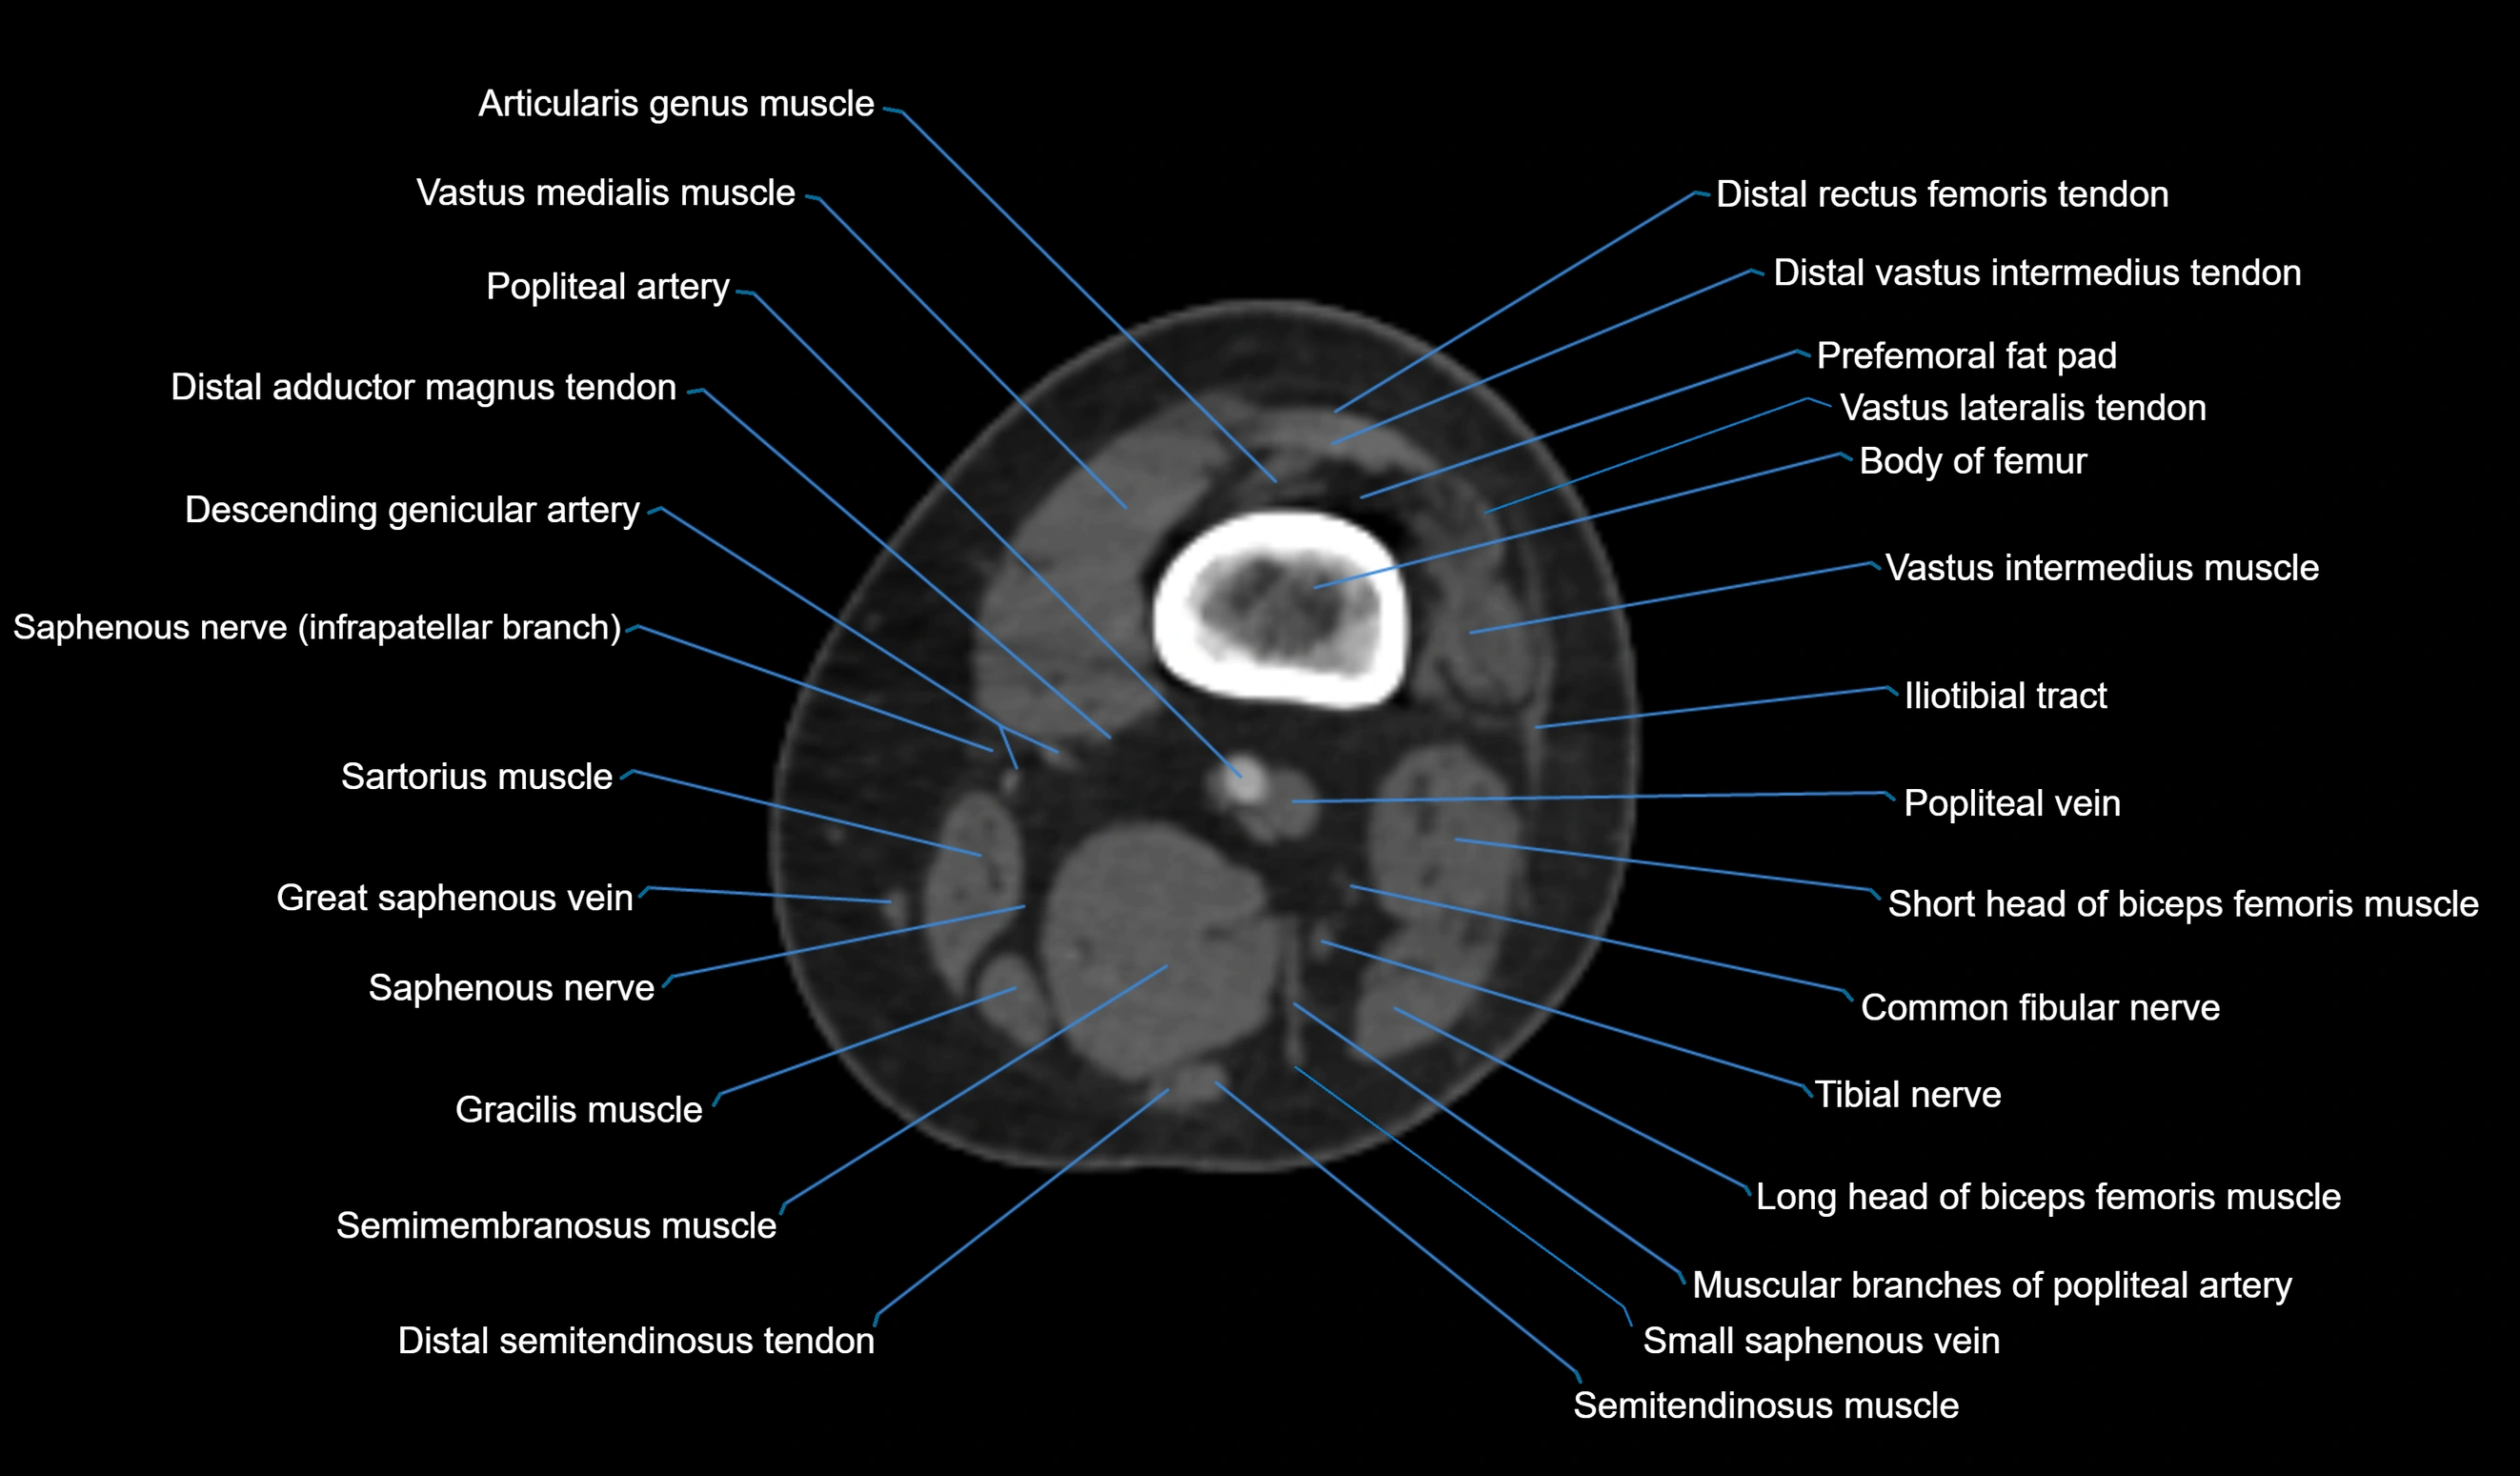

- Biceps femoris muscle (Long head)

- Biceps femoris muscle (Short head)

- Body of femur

- Distal adductor magnus tendon

- Distal rectus femoris tendon

- Distal vastus intermedius tendon

- Distal vastus lateralis tendon

- Popliteal artery

- Popliteal vein

- Prefemoral fat pad

- Saphenous nerve

- Sartorius muscle

- Semimembranosus muscle

- Semitendinosus muscle

- Small saphenous vein

- Tibial nerve

- Vastus lateralis muscle

- Vastus medialis muscle